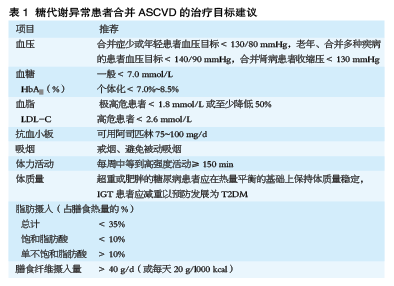

进行多重危险因素管理

指南强调,对于存在糖代谢异常的患者,要进行多重危险因素管理。指南建议,应尽早评估下列情况,并保证治疗达标。例如,吸烟、高血压和血脂异常等危险因素,微血管和大血管病变,心衰和心律失常等合并症,心肌缺血及左心室功能等。对于各项治疗目标值,指南也提出了具体的建议(表1)。